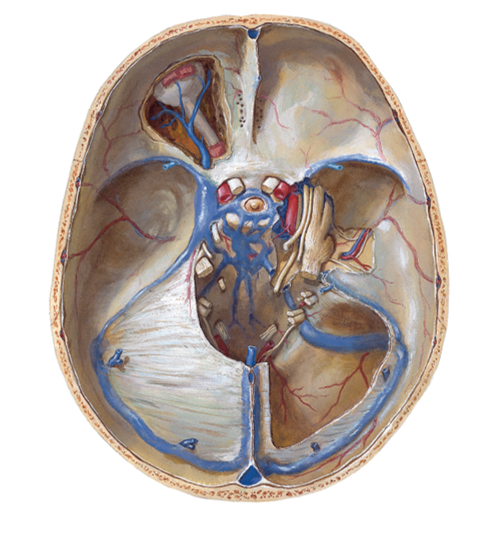

Анатомия внутренней яремной вены: КТ изображения